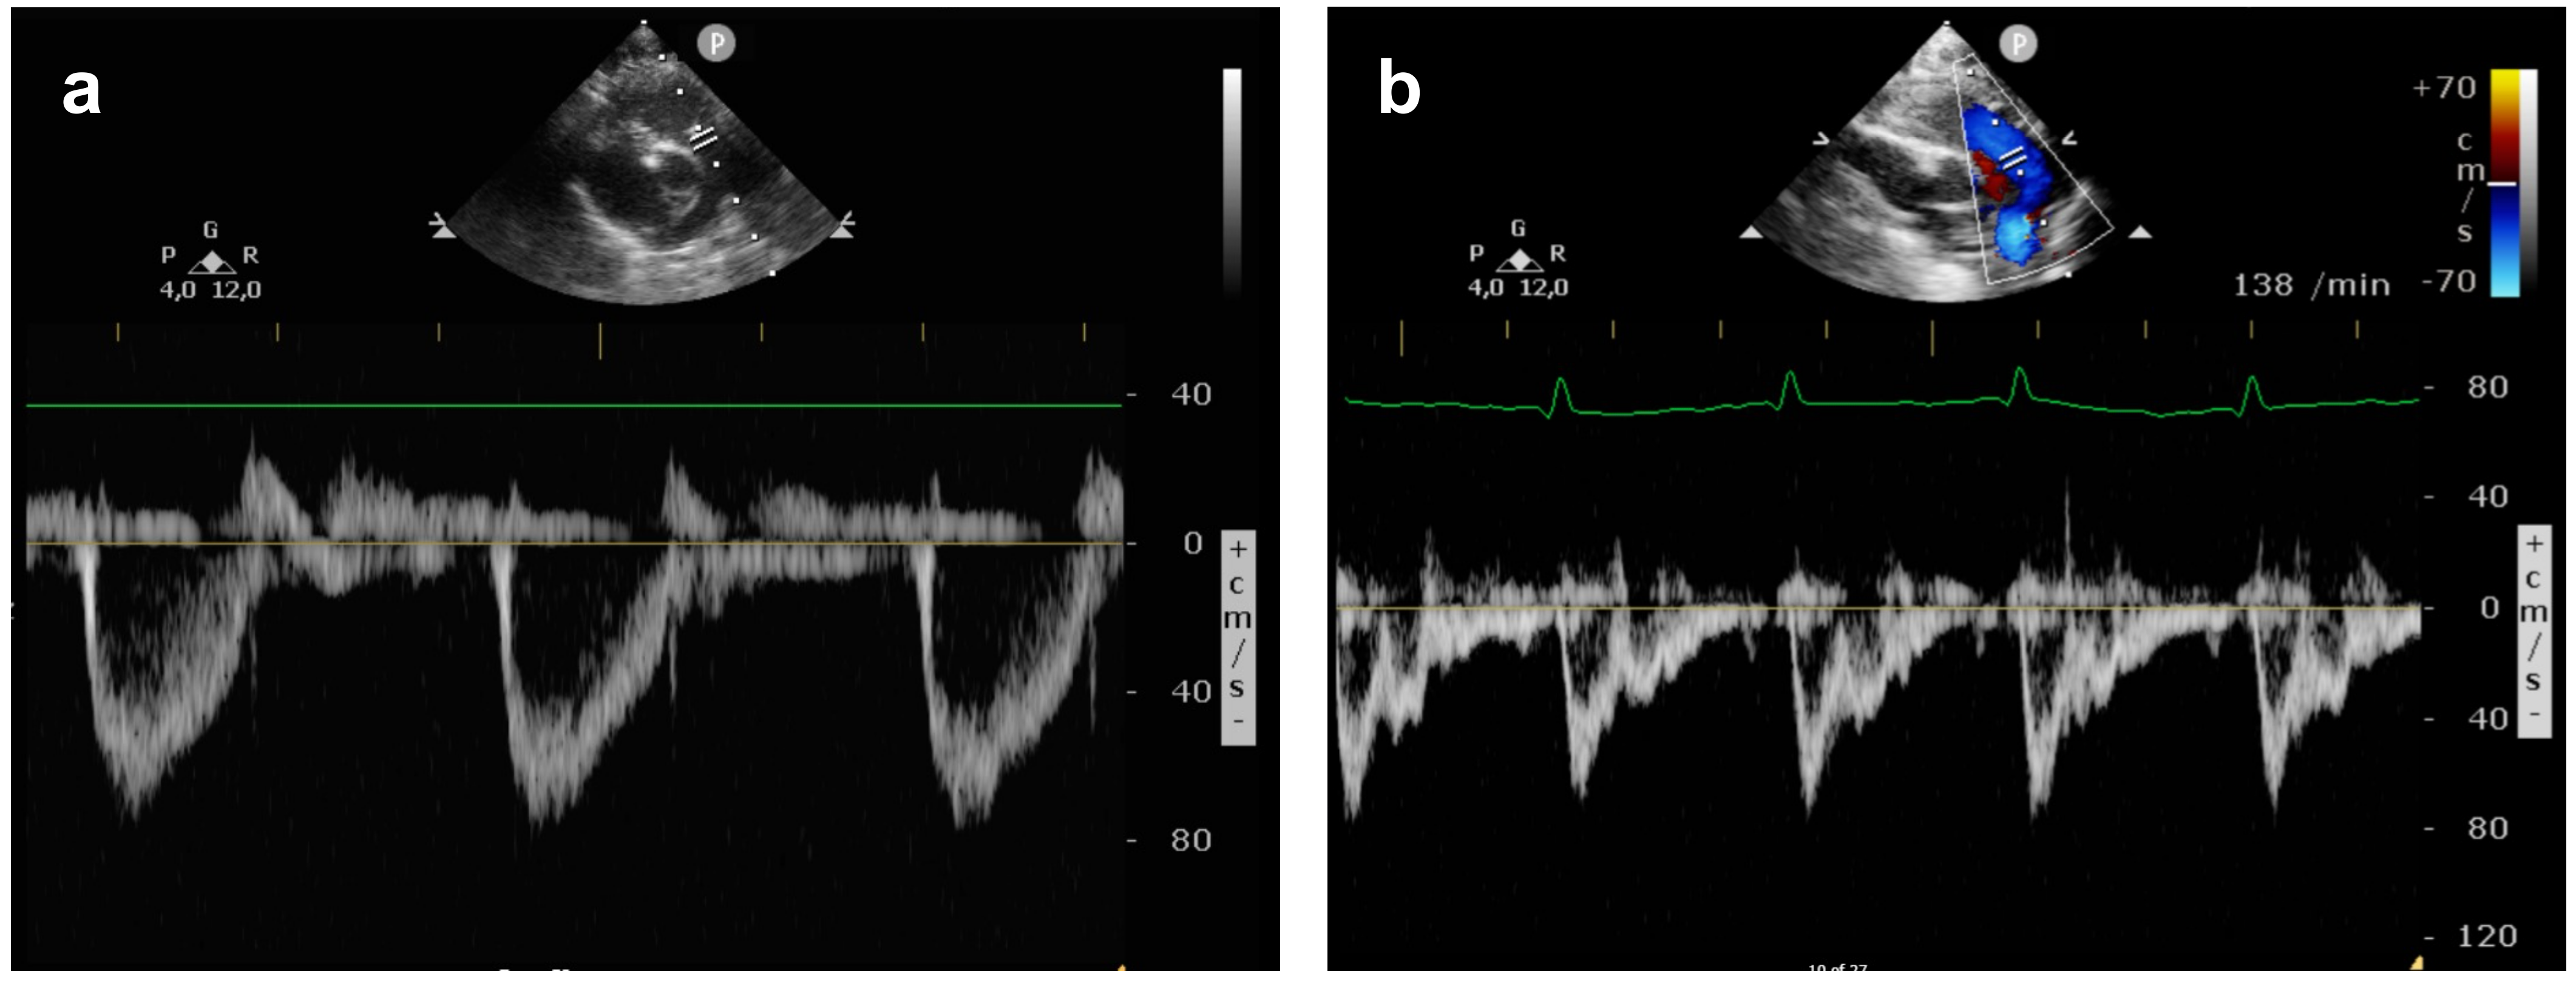

2.3. Echocardiography Data